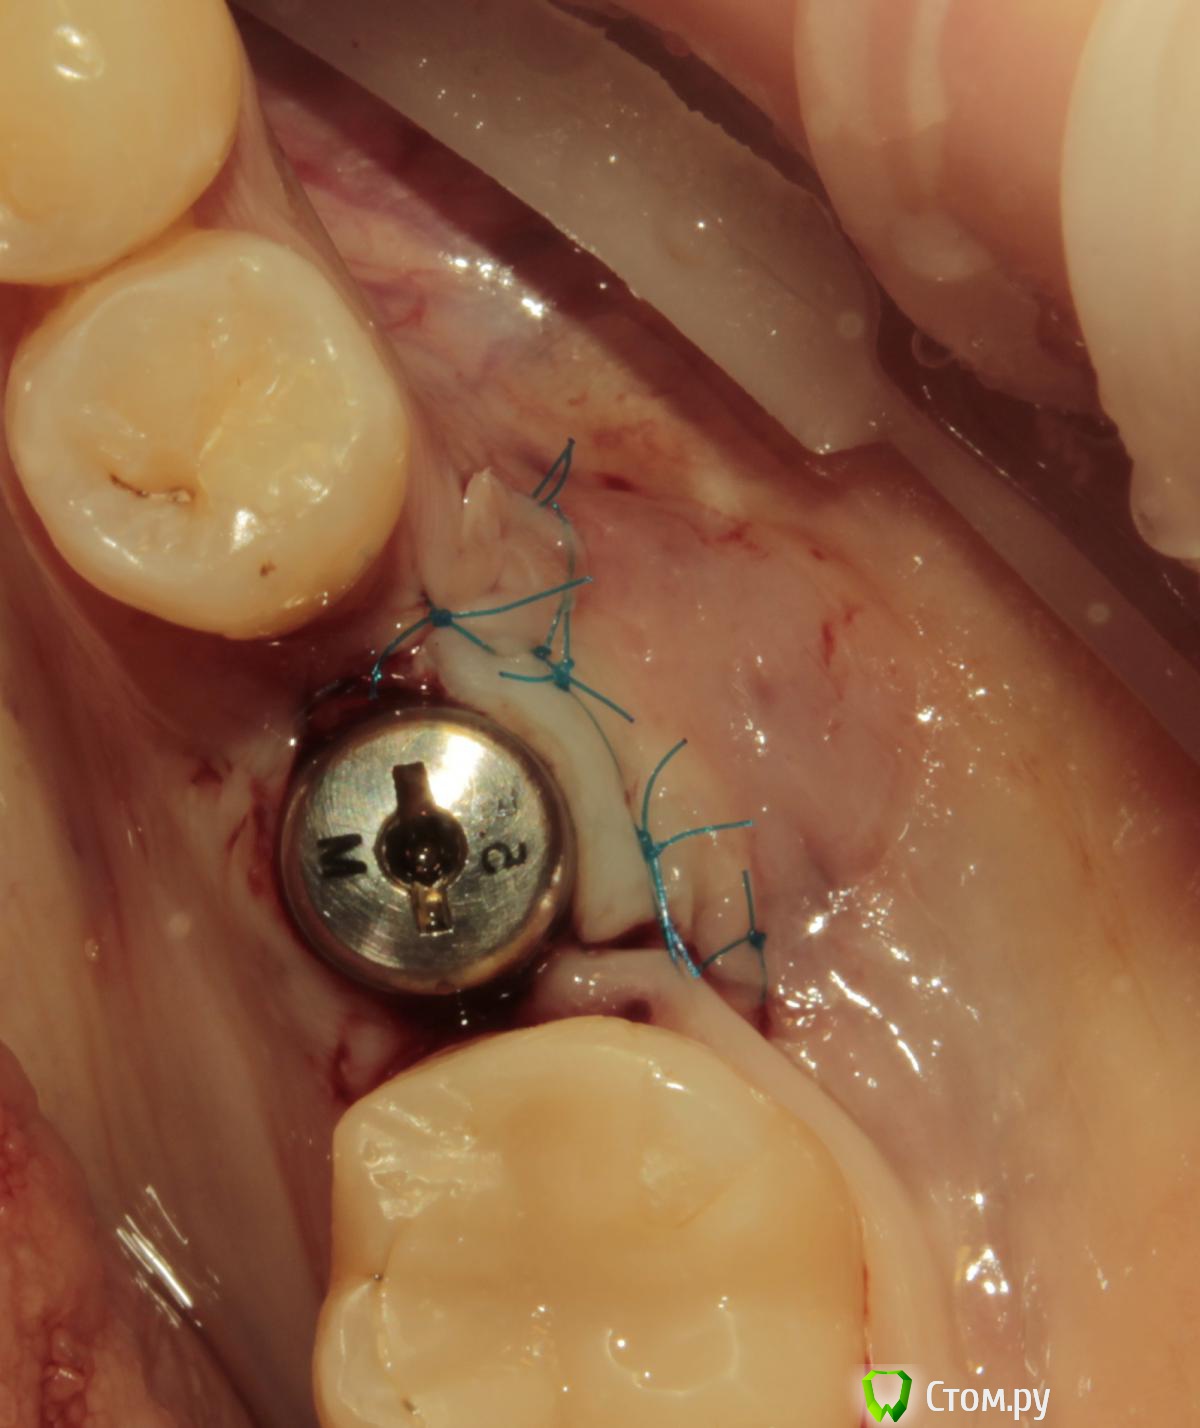

Acidrocker Опубликовано 13 мая, 2014 Поделиться Опубликовано 13 мая, 2014 Вот такой круассан получил на днях. На раскрытии имплантата под расщепленный лоскут уложил сст с бугра. Вид после снятия швов через 3 недели. 11 Ссылка на комментарий